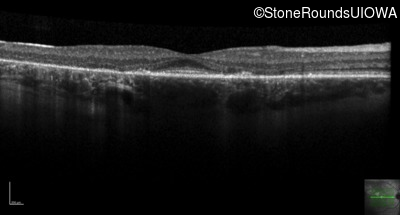

Age at visit: 30 years

This 30 year old man first noticed poor vision in dim light when he was five years old. His visual acuity began to fall in his early 20's.